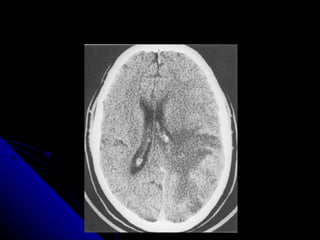

CAUSAS DE AFASIA 1.- infartos y hemorragias 2.- Neoplasias primarias o metastasicas 3.- demencias Pick y Alzheimer 4.- lesiones traumáticas